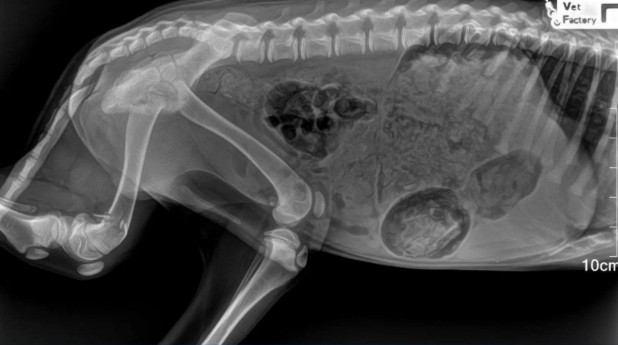

"Вопиющий случай": душераздирающий инцидент с собакой в Приморье — подробности

Полиция ищет злоумышленника, возбуждено уголовное дело